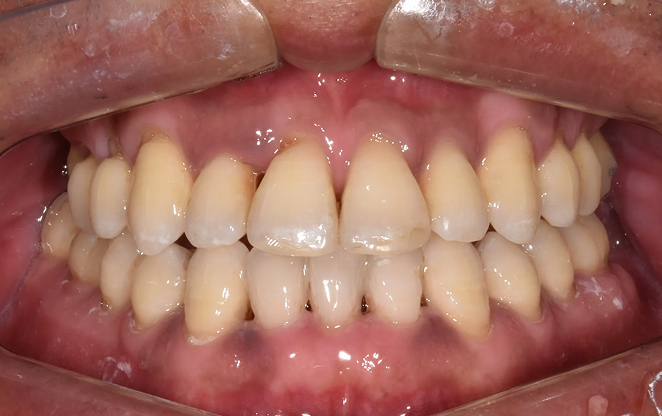

Before

After